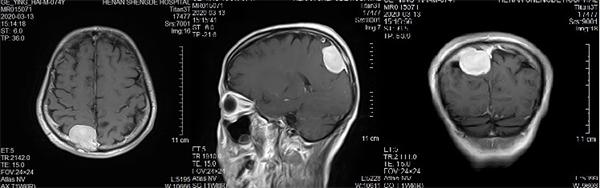

术前核磁共振检查

映象网信阳讯(记者 吴彦飞 通讯员 吴琼 曹启合)日前,74岁的葛大爷,因“发作性头晕5年”,在居住当地医院行颅脑MRI(核磁共振)提示颅内占位。紧急转入河南圣德医院神经外科,行MRI提示:矢状窦旁脑膜瘤。

入院后河南圣德医院副院长兼神经外科主任于耀宇查看患者病情,告知其家属脑肿瘤直径较大,压迫功能区,且与上矢状窦粘连,占位效应明显,有明确手术指征,但手术风险较大,手术过程有可能造成上矢状窦大出血及部分神经功能缺失,家属商量后同意手术。